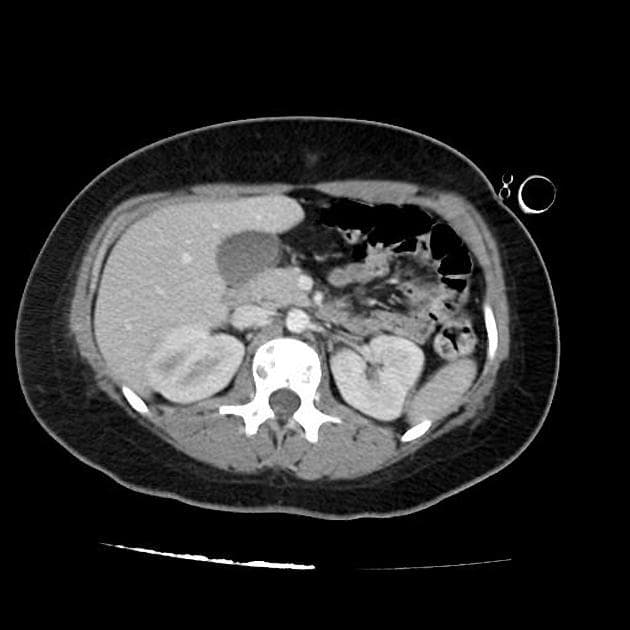

- Khối bất thường kích thước gần 9 cm ở tâm nhĩ phải, tăng quang không đồng nhất, gây hẹp đoạn nối giữa tĩnh mạch chủ trên và tâm nhĩ phải (superior cavoatrial junction).

- Khối xâm lấn màng ngoài tim với hình ảnh dày lên dạng nốt (nodular pericardial thickening) và vệt tăng tỷ trọng ở mỡ màng ngoài tim (pericardial fat stranding).

- Hơn 20 nốt nhỏ ở mỗi phổi, kích thước tối đa 6 mm, nhiều nốt có vùng mờ kính (ground-glass attenuation) xung quanh, gợi ý bệnh lý di căn xuất huyết (hemorrhagic metastatic disease).

- Tràn dịch màng phổi (pleural effusion) hai bên, lượng ít.

Hình ảnh điển hình của u ác tính mạch máu tim (angiosarcoma): các khối u ác tính nguyên phát tại tim thường gặp ở tâm nhĩ phải và xâm lấn màng ngoài tim. Các nốt phổi cho thấy bệnh lý di căn đến phổi (metastatic disease to lung).